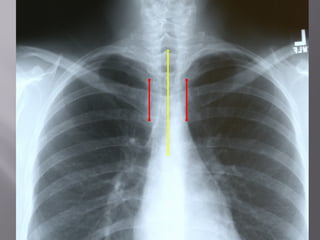

 7. Rotation

 Medial ends of

bilateral clavicles are

equidistant from the

midline or vertebral

bodies

If spinous process appears closer to the right clavicle (red arrow),

the patient is rotated toward their own left side

If spinous process appears closer to the left clavicle (red arrow),

the patient is rotated toward their own right side